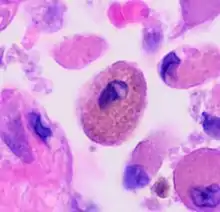

The uptake of tar from cigarettes accumulates in alveolar macrophages and causes autofluorescence.[4] The intensity of fluorescence, however, is independent of cigarette exposure. This indicates a maximum capacity of tar uptake; excess tar cannot be retained by macrophages. Another pigment in smoker’s macrophage is hemosiderin which is involved in iron homoeostasis. Hemosiderin-laden pigmented macrophages are yellowish brown and found in the bronchiole and peribronchiolar alveolar space.[9] The presence of these dirty macrophages has been a characteristic of many smoke-related lung diseases.[9][10]